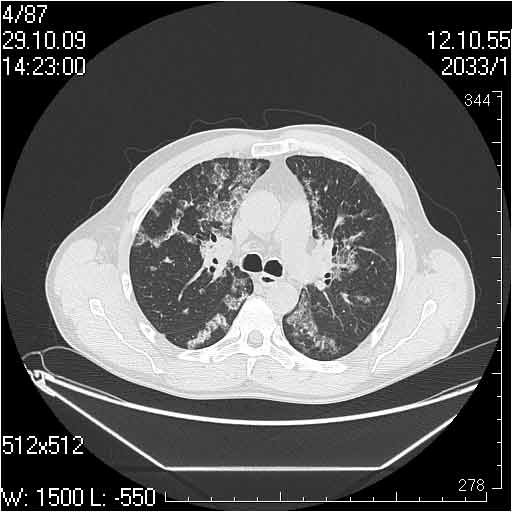

Случай №1

Женщина 50 лет.

Случай 1: изменения характерны для интерстициальной пневмонии (IIP/UIP idiopathic interstitial pneumonia/usual interstitial pneumonia); говорить о конкретной форме без открытой биопсии затруднительно.